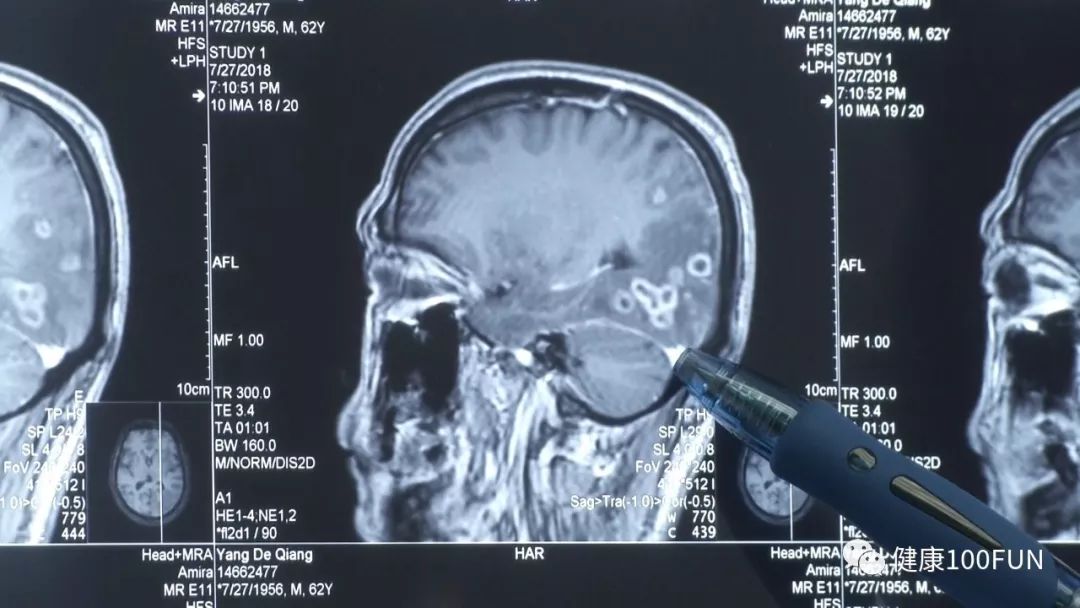

广州街坊强叔,在跟朋友吃饭时突然晕倒,送院途中四肢抽搐,住院后出现意识不清、记忆下降等精神性癫痫症状。经过影像学的检查以及流行病学史研究发现,在强叔的颅内有明显的病变,后确诊为裂头蚴。

经过医生的仔细询问,原来强叔特别喜欢吃生鲜食物,比如鱼生、蛇、田鸡、蛤蟆等。

(强叔颅内裂头蚴位置)